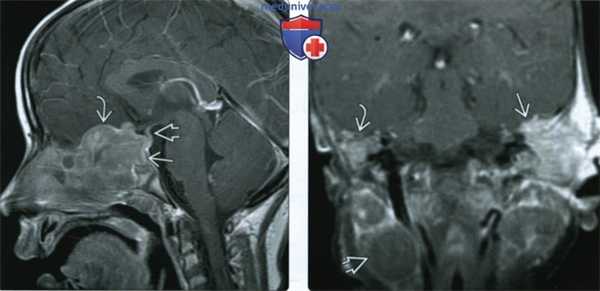

(Слева) МРТ, постконтрастное Т1-ВИ, режим подавления сигнала от жира, сагиттальный срез: у пятилетнего мальчика с хроническими головными болями и несахарными диабетом определяется гетерогенно накапливающее контрастное вещество поражение центральных отделов основания черепа. Обратите внимание на утолщение и смещение воронки гипофиза.

(Справа) МРТ, FLAIR, аксиальный срез: у шестилетнего мальчика с нарушением поведения, в белом веществе мозжечка определяются сливные гиперинтенсивные зоны демиелинизации. Обратите внимание на вовлечение в процесс ядер отводящих нервов.

(Слева) При МРТ Т1 с КУ в сагиттальной проекции в центральной области основания черепа определяется крупное неравномерно контрастируемое образование, распространяющееся в турецкое седло (ЛКГ). Обратите внимание на интракраниальное распространение патологического процесса в переднюю ямку через клиновидную площадку и поражение воронки гипофиза.

(Справа) При МРТ Т1 с КУ в корональной проекции у пациента с ЛКГ определяются объемные образования обеих височных костей. Слева новообразование неправильной формы прорастает твердую мозговую оболочку, тогда как справа распространяется только до ее поверхности. Справа видны неравномерно контрастируемые увеличенные шейные лимфоузлы.